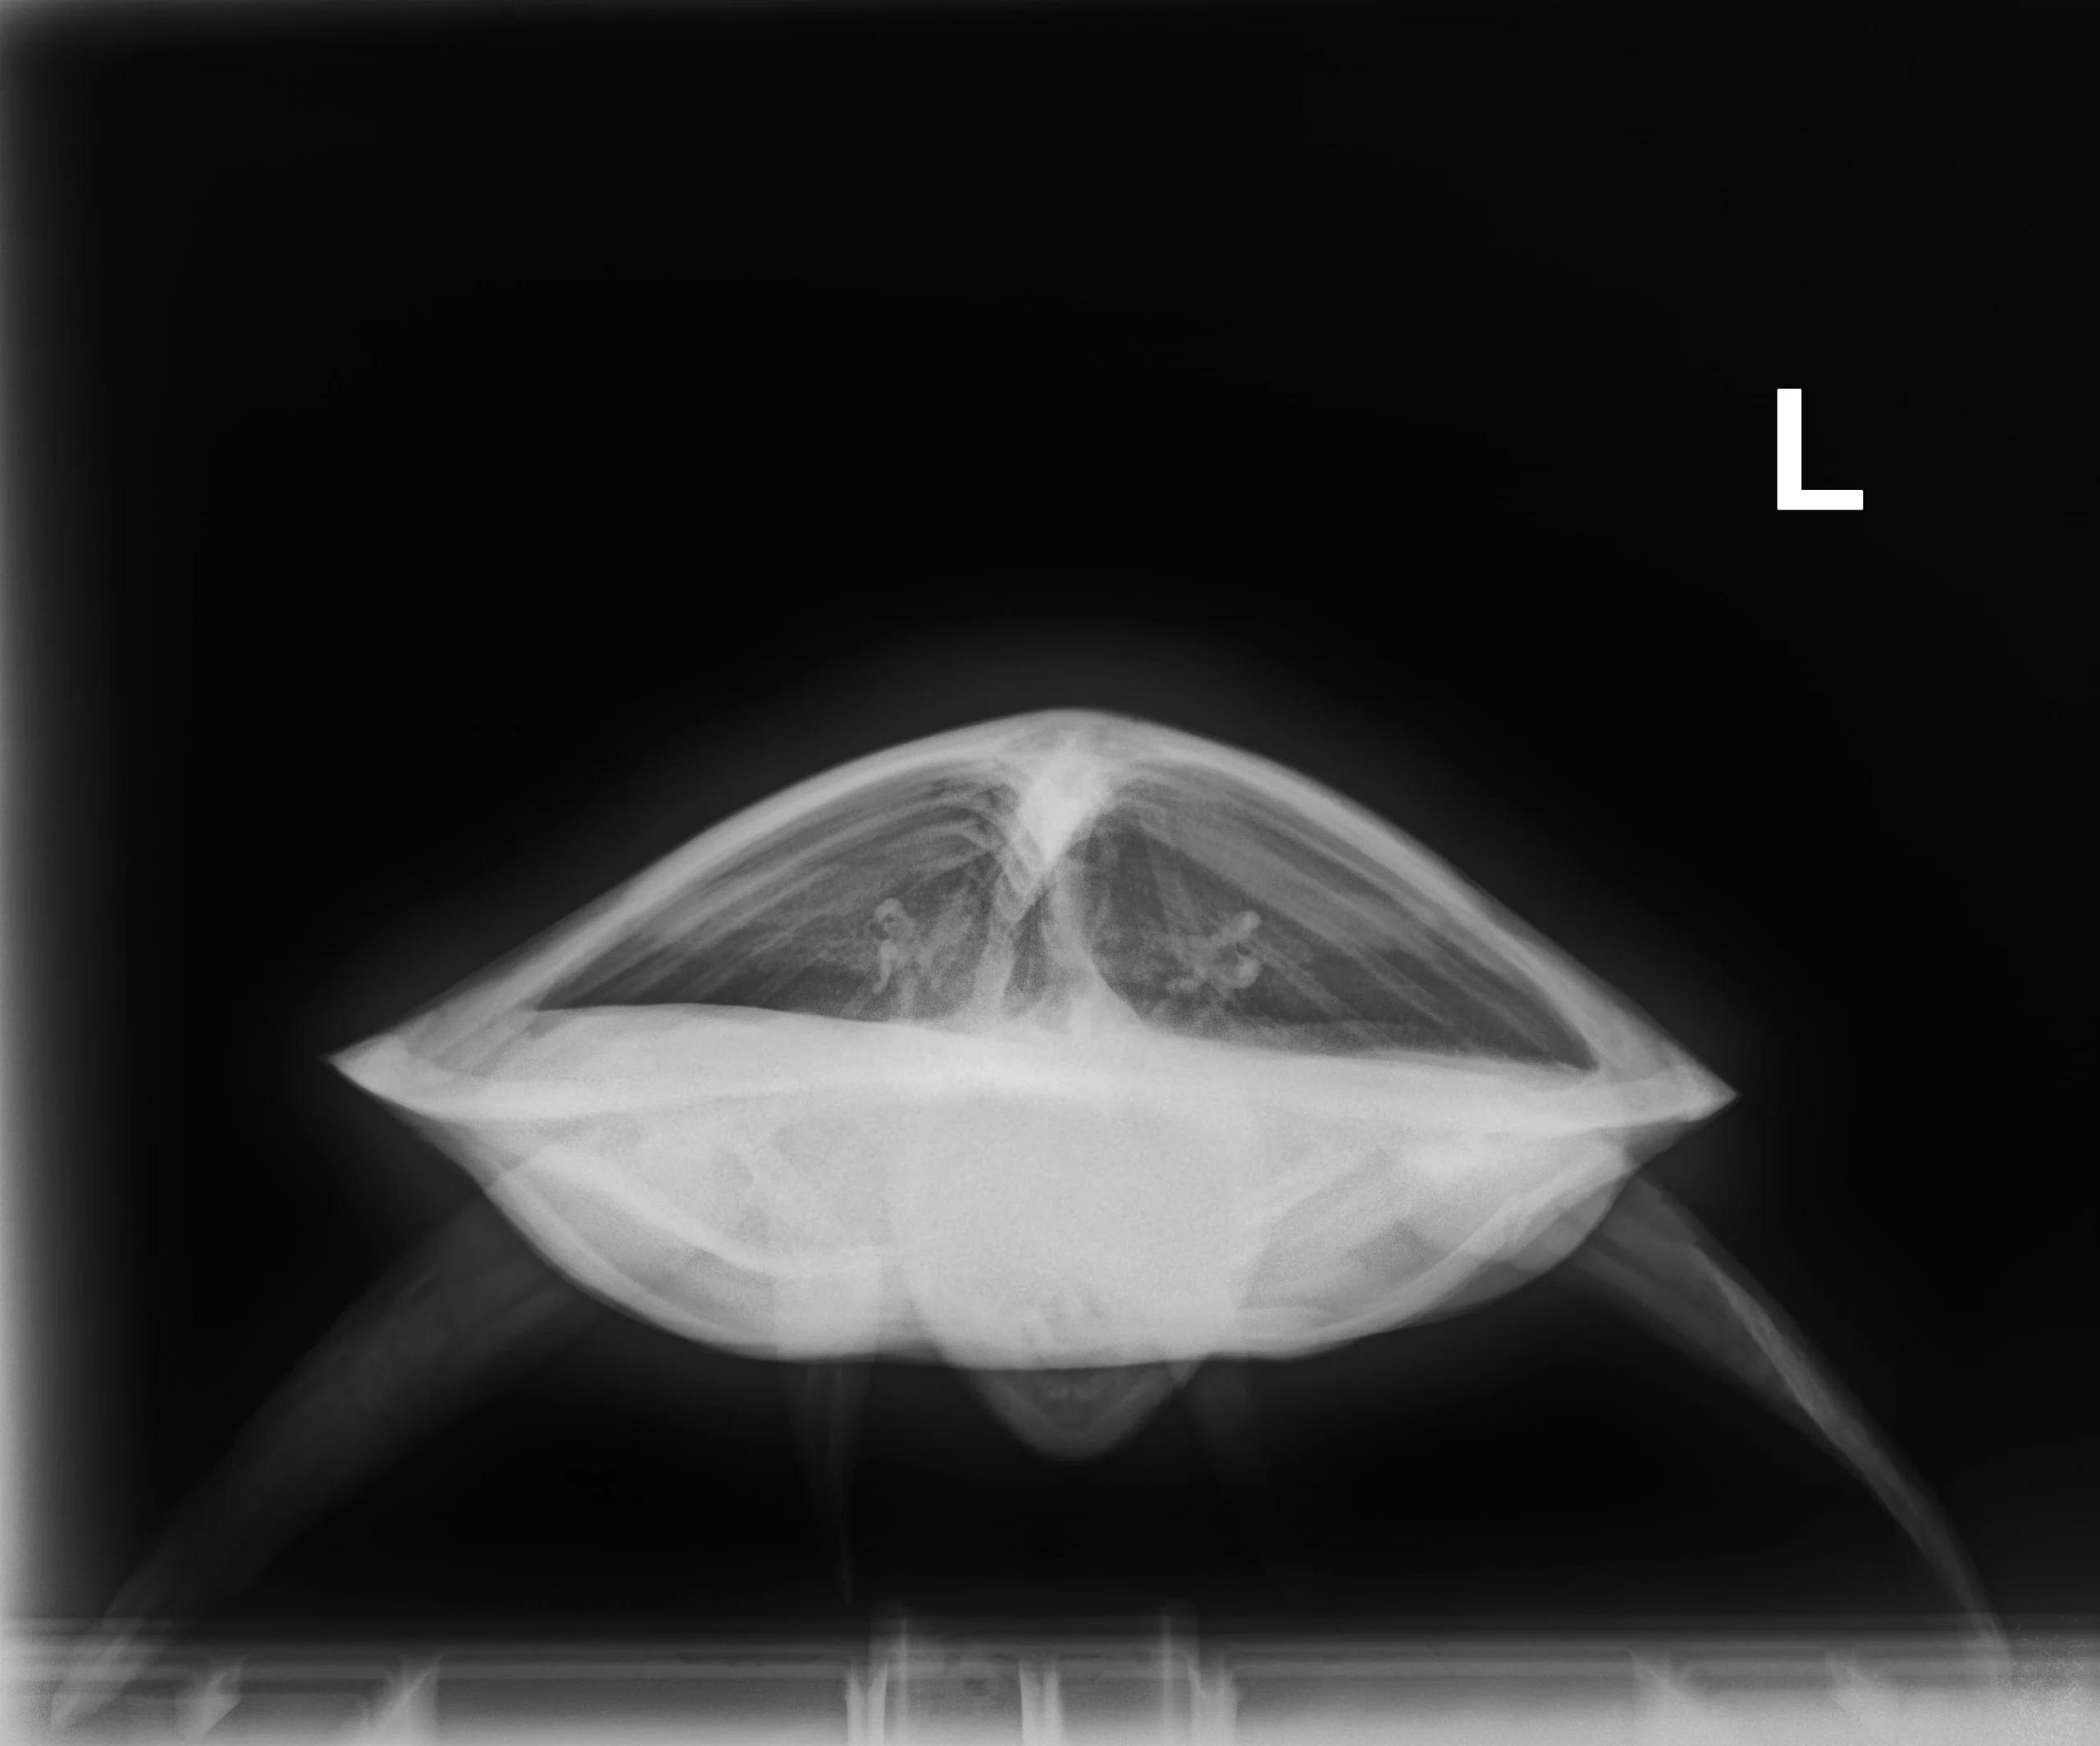

3.20 kg juvenile Atlantic Green sea turtle

Patient Injuries

External Carapace Notes: Scrapes on the caudal end of the marginal scutes, moderate abrasions towards the center

Plastron: Severe abrasions, scrapes on caudal end, abrasions on the marginal scutes

External Wounds: Abrasion to chin